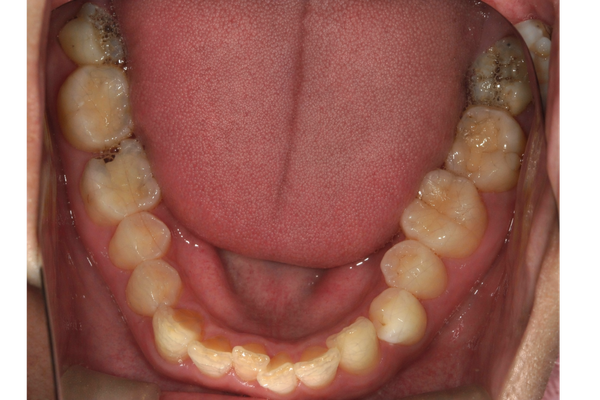

Before

| 通院目的 | 歯が欠けてしまい、そこに食べ物が詰まって食事が苦痛だった。 |

| 処置内容 | 欠けた部分から虫歯が進行していたため、根の治療を行い、土台を作り直し仮歯を装着。 その後、精密な型取りを行い、自然な色調再現性と適合性に優れたオールセラミッククラウンで最終補綴物を製作・装着しました。 |